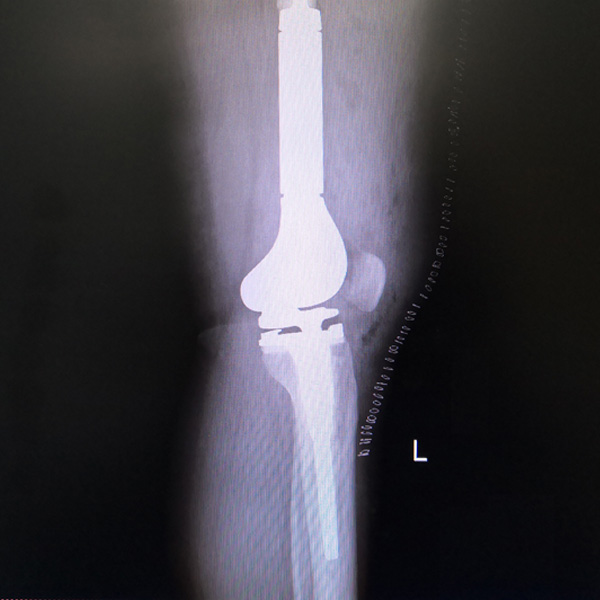

手術(shù)后手術(shù)前

膝關(guān)節(jié)內(nèi)翻

患者劉某某,女66歲,左側(cè)膝關(guān)節(jié)嚴(yán)重內(nèi)翻(俗稱的“羅圈腿”),疼痛到不能生活自理。經(jīng)平臺推薦到哈爾濱醫(yī)科大學(xué)附屬第二醫(yī)院骨關(guān)節(jié)科就診,......